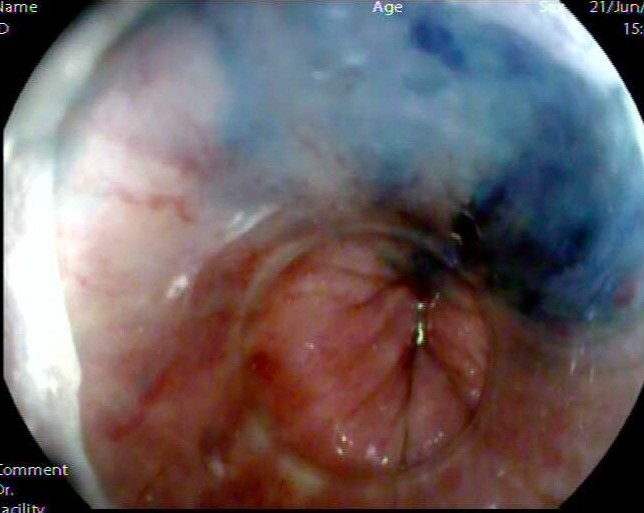

消化内科二病区主任刘祖明手术画面

http://10.1.8.51/supesite/attachments/2019/07/1_201907190916203WuqP.jpg